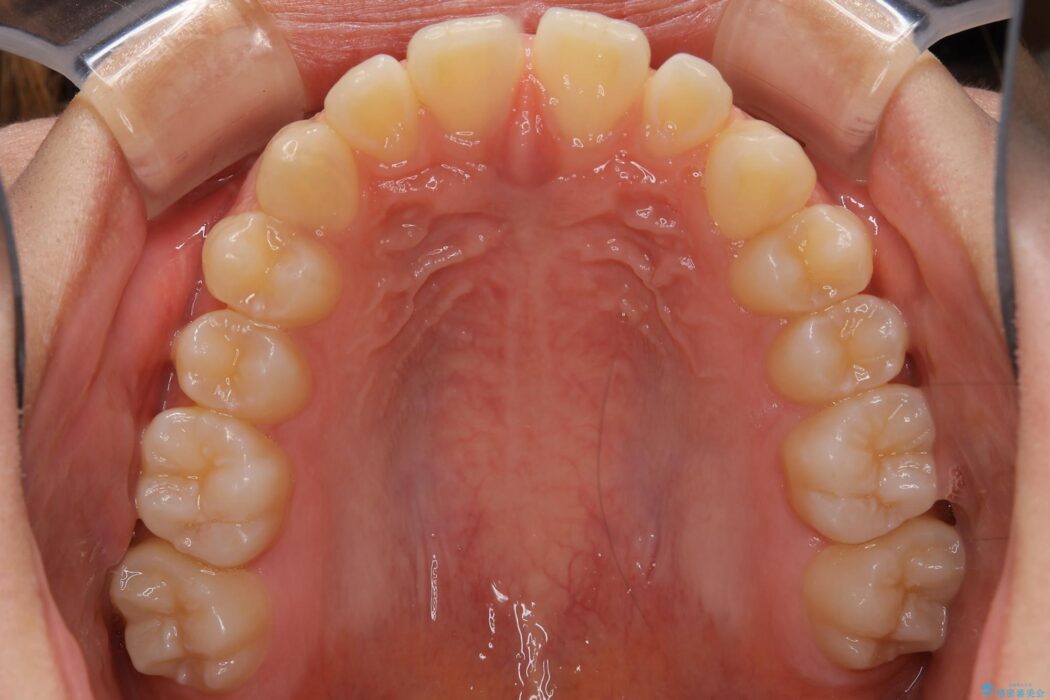

すきっ歯を改善したいとご来院された患者様です。

マウスピース14枚・期間4ヶ月で主訴であるすきっ歯を改善し、治療を終えることが出来ました。